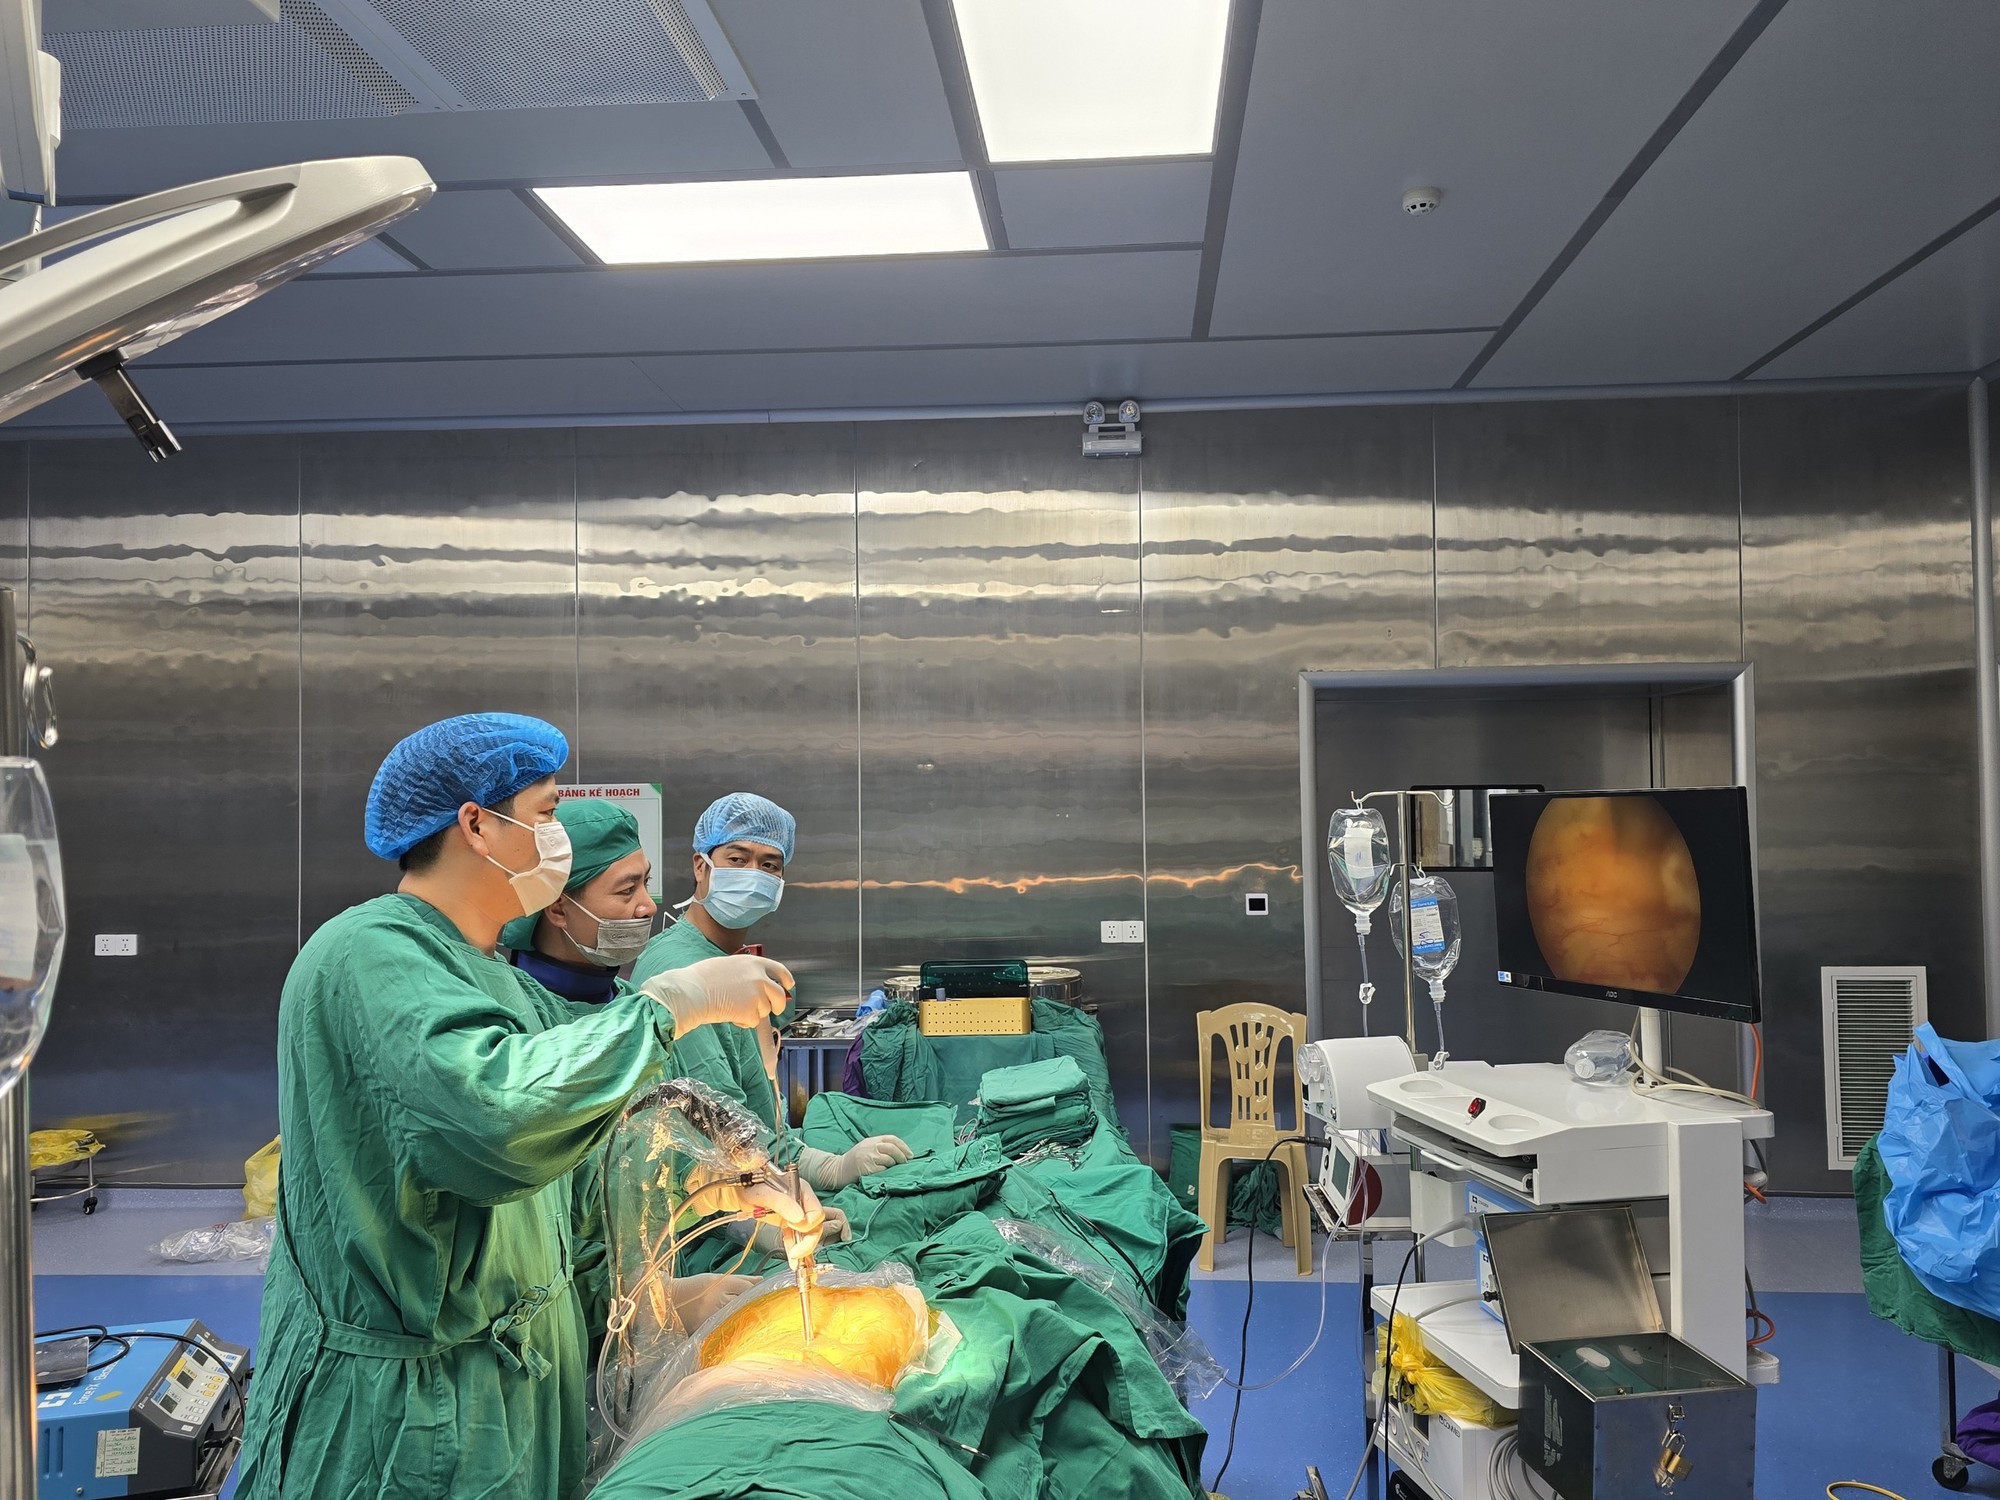

ក្រុមគ្រូពេទ្យនៃនាយកដ្ឋានវះកាត់សរសៃប្រសាទ thoracic បានធ្វើការវះកាត់លើអ្នកជំងឺ T.

ដោយការបើកស្នាមវះតូចមួយប្រហែល 1cm នៅលើស្បែក វេជ្ជបណ្ឌិតបានបញ្ចូល endoscope និងឧបករណ៍វះកាត់ដើម្បីចូលទៅដល់ឆ្អឹងខ្នង និងបន្ថយសម្ពាធលើសរសៃប្រសាទ និងខួរឆ្អឹងខ្នង។

ដោយមានការគាំទ្រពីប្រព័ន្ធ C-arm ដ៏ទំនើប បន្ទាប់ពីរយៈពេល 1 ម៉ោង ក្រុមវេជ្ជបណ្ឌិតបានធ្វើការវះកាត់ដោយជោគជ័យ ដើម្បីយកដុំសាច់ដែលដុះចេញ និងបន្ធូរសម្ពាធលើសរសៃប្រសាទ និងខួរឆ្អឹងខ្នងរបស់អ្នកជំងឺ (ខាងស្តាំ L5 lateral recess)។